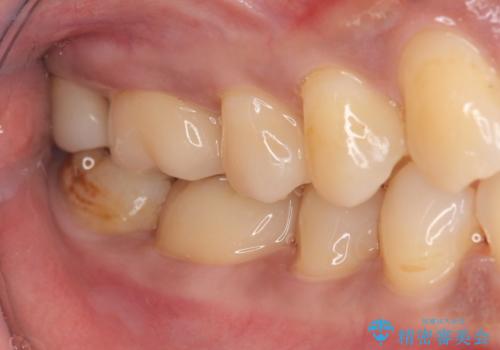

- 口の中に見える銀歯を、金属アレルギーの対策と審美性の向上のため全て除去したい!と希望され来院されました。

銀歯を丁寧に除去したのち、精度の良いセラミックインレー、セラミッククラウンで修復・補綴処置を行っていきます。

- 62.7万円(ジルコニアクラウン×3・仮歯×3・セラミックインレー×3)費用は治療当時の料金となります